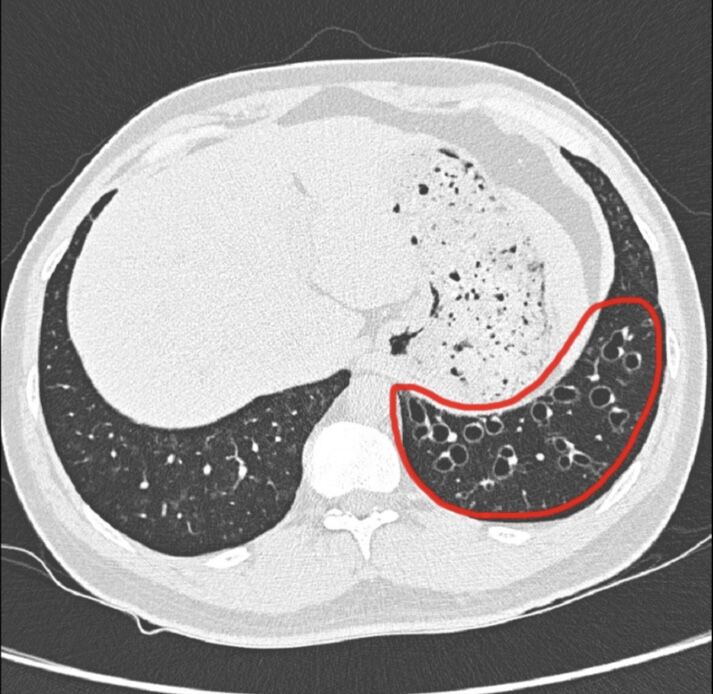

如果能夠持之以恆,早晚各做一次「肺復原氣道清潔」,約3到6個月,就能從電腦斷層的影像中,清楚看到已經擴張的支氣管內痰液,顯著減少。同時相關的症狀,像是濃痰、喘、胸悶,也能有明確的症狀改善。